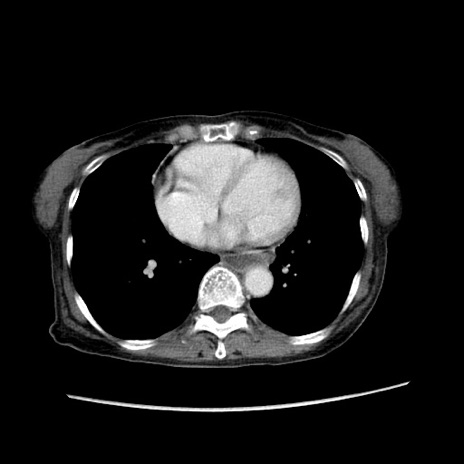

冠状断像

【症例】80歳代女性

【主訴】胸のつかえ感

【現病歴】約9時間前に食後から胸のつかえた感じあり、嘔吐あり、来院。

【既往歴】胃癌(全摘)、胆摘、虫垂炎

【身体所見】心窩部に圧痛あり、反跳痛なし。

【データ】WBC 5700、CRP 0.05